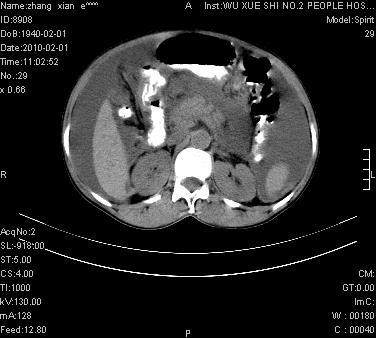

标题: CT24434:70岁 女 腹胀,腹水原因待查 [打印本页]

标题: CT24434:70岁 女 腹胀,腹水原因待查

大量腹水,脾囊肿可能性大,建议增强

腹盆腔大量积液,子宫增大,子宫颈增大外形不规则,内见低密度影,膀胱后壁显示不清,右腹股沟肿大淋巴结,脾脏囊性占位,子宫颈占位,子宫颈癌?建议增强。

大量腹水,右肾、脾囊肿可能性大          考虑左侧附件区占位,建议增强